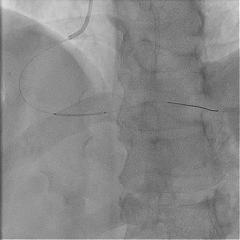

PCI术后即刻将压力导丝送至RCA远端,测得RCA IMR 63(+),FFR 0.94,表明RCA存在CMD。

▶ RCA IMR 63(+),FFR 0.94。